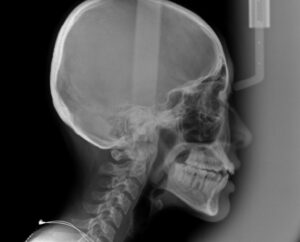

でっ歯の度合いを調べる横からのレントゲン

セファロを撮影